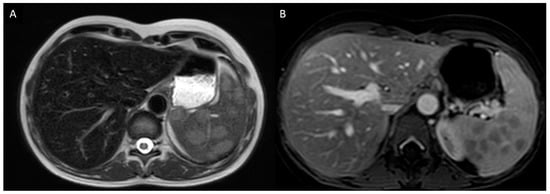

3.2.1. Case Description

| 8 | M | 53 | Caucasian | Granulomatous kidney (renal failure) and liver disease (cirrhosis and portal hypertension). Mesenteric and cervical lymph nodes. Monoclonal gammopathy. | Exclusive extrathoracic disease with severe renal involvement. | 47 months | Multiple myeloma | Granulomatosis was treated with corticosteroids, azathioprine and mycophenolate mofetil without clear improvement. | The patient died a few days after trans jugular portal shunt procedure. |